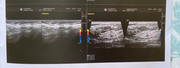

Presenza al QSE dx di una formazione ipo/isoecogena a margini ben delimitati di 7x4 mm, non vascolarizzata al color-Doppler.

Tale reperto risulta essere compatibile con fibroadenoma, utile monitoraggio ecografico annuale.

e questa è l’ecografia effettuata